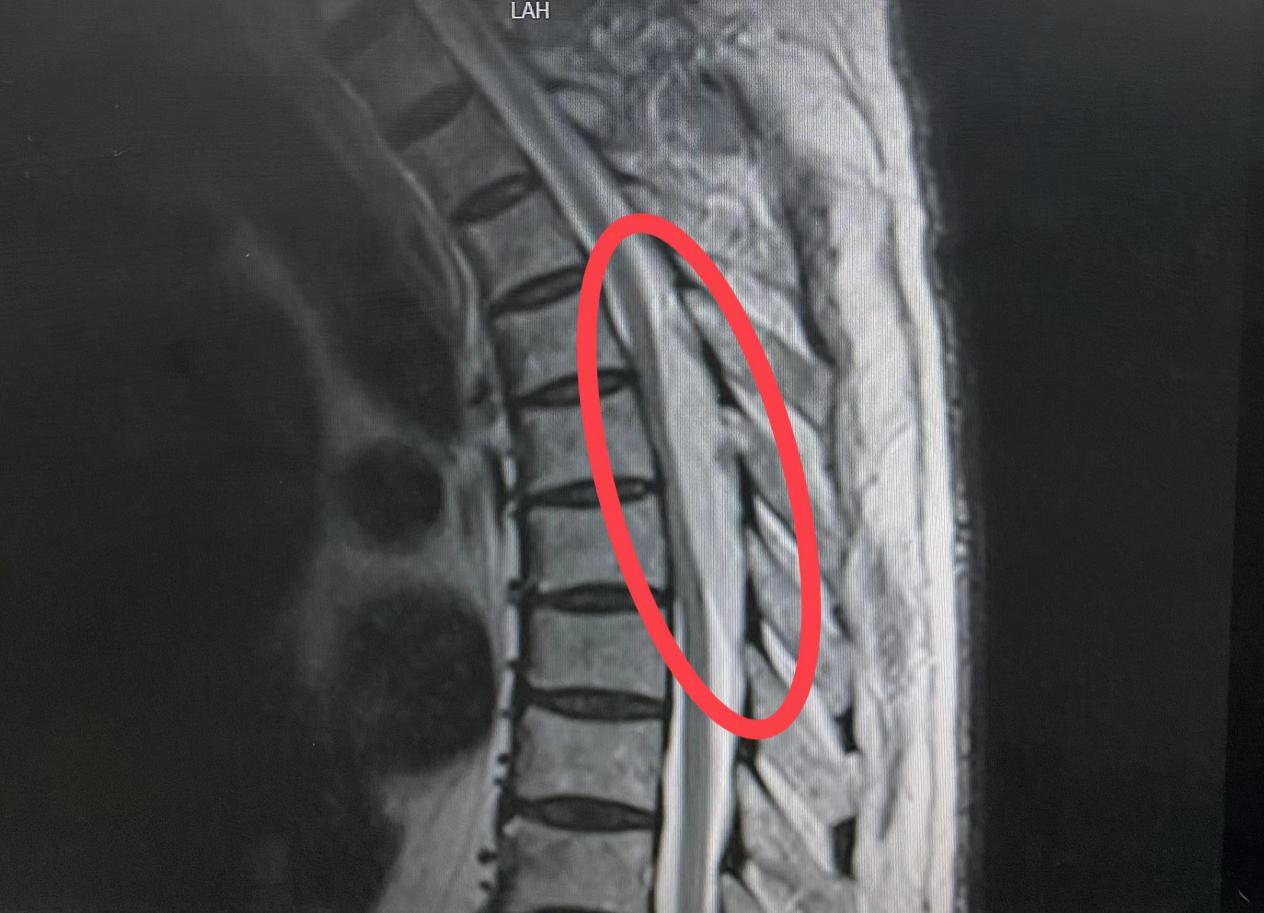

患者男性,66岁,1年前患者无明显诱因出现双下肢无力、麻木等症状,活动稍受限,多方治疗效果不佳。1月前,感足趾僵硬,并逐渐向上延伸至膝关节,同时伴小便失禁,查体见患者步态不稳、行走缓慢,步距小,踝关节及足趾跖屈力量减弱,脐以下感觉明显减退。入院后行胸椎MRI检查提示胸4-7椎体水平椎管内占位性病变,结合影像学资料综合考虑血管脂肪瘤。

由于患者的肿瘤位于胸4-7椎体水平,术前检查提示肿瘤血供丰富,肿瘤体积大,脊髓明显受压变薄,且下肢已出现不全瘫,括约肌功能受损,任何小的牵拉、刺激都可能损伤脊髓致肌力进一步下降,甚至截瘫,严重影响患者生存质量。加上此类疾病十分罕见,因此患者入院后科室高度重视。